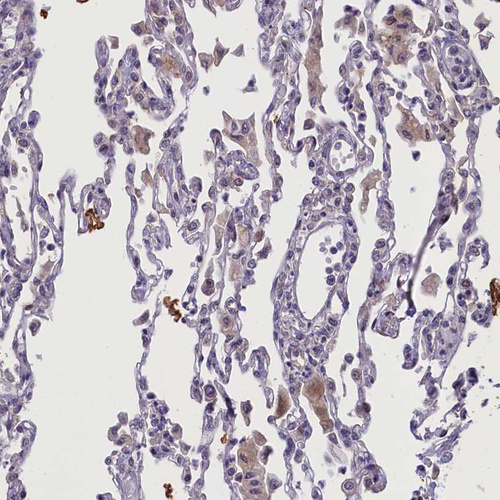

Immunohistochemical staining of human lung shows very weak cytoplasmic positivity in macrophages.